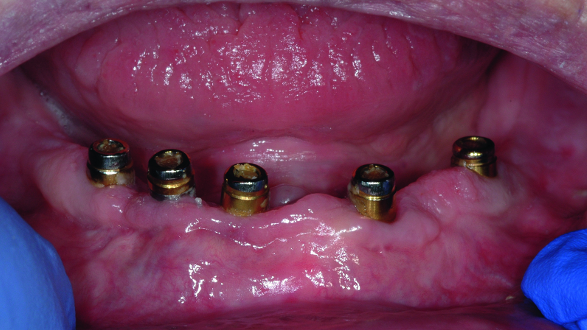

Fig. 2: Clinical image of patient. Note the wear of the metal abutments due to disengagement of the nylon retention inserts as a result of fulcrum during function.

The patient continued to experience problems with the lower denture coming loose during function and required frequent replacement of the nylon male inserts; replacement with Extended Range inserts did not vary performance. The metal abutments demonstrated considerable wear as well (Fig. 2). Relining the lower denture did not improve the performance of the anchor system.